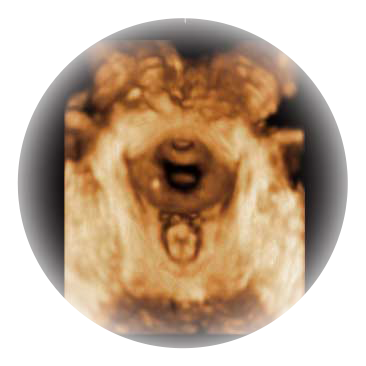

可同时显示组织结构表面和内部的轮廓信息,达到透视效果,为临床提供更丰富的诊断信息。

大角度腔内容积探头,可完整包络子宫及盆底结构,充分展示组织结构毗邻关系。